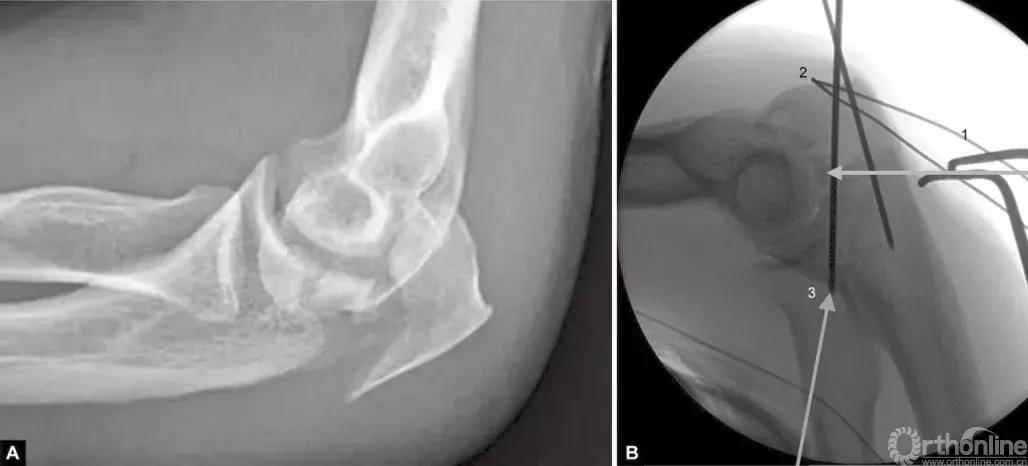

图1A~C(A)关节压缩骨折不易觉察,有经验的医生会注意到从冠状突到鹰嘴尖的关节间隙增宽而得出诊断;(B)如果没有的观察力,医生甚至会在术中X线片检查中都漏诊明显的压缩骨折。医生的注意力完全集中在检查植入物的位置上,因此容易忽略关节不一致;(C)术后摄片显示压缩骨折未复位